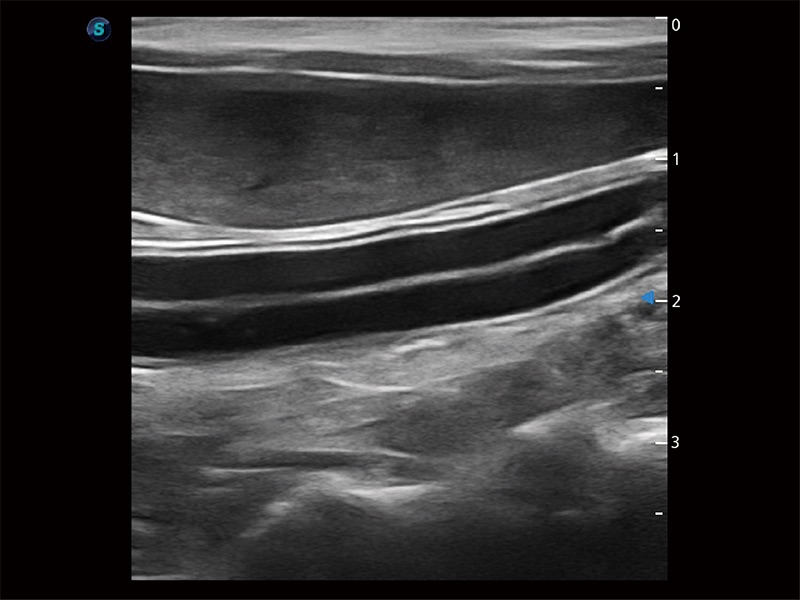

极大提升超低速微细血流的检出能力,同时更精准地滤除软组织和超声信号,为兽用医生提供以往无法通过常规血流获得的疾病诊断信息。

在传统二维血流成像的基础上,呈现血流的立体感,具有动感的生命力之美。即便是微小的血管也能轻松应对,提高了血流的视觉敏感性。

操作简便,无需高频度外力作用即可真实反映组织的形变,快速评估肿瘤良恶性。

为精细结构及组织边缘提供高清晰度的图像和更大的成像视野。帮助减轻医生的用眼疲劳,快速精准获得测量的数据。